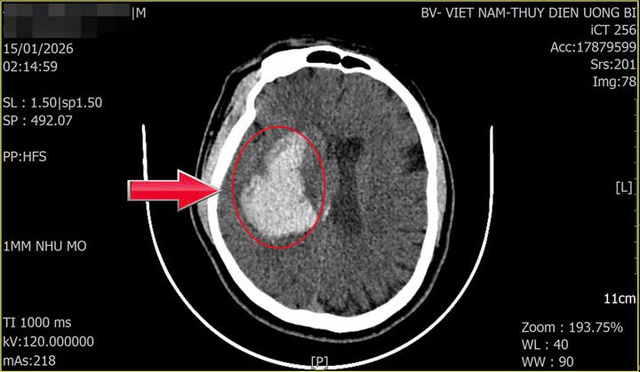

Khối máu tụ của người bệnh (vị trí mũi tên chỉ). Ảnh: BVCC

Ngay sau khi tiếp nhận, người bệnh được chụp CT sọ não cấp cứu. Kết quả cho thấy hình ảnh xuất huyết não kèm tụ máu trong nhu mô não, gây chèn ép tổ chức não xung quanh. Trước diễn biến nặng và nguy cơ đe dọa tính mạng, các bác sĩ đã nhanh chóng hội chẩn và quyết định phẫu thuật cấp cứu lấy khối máu tụ.